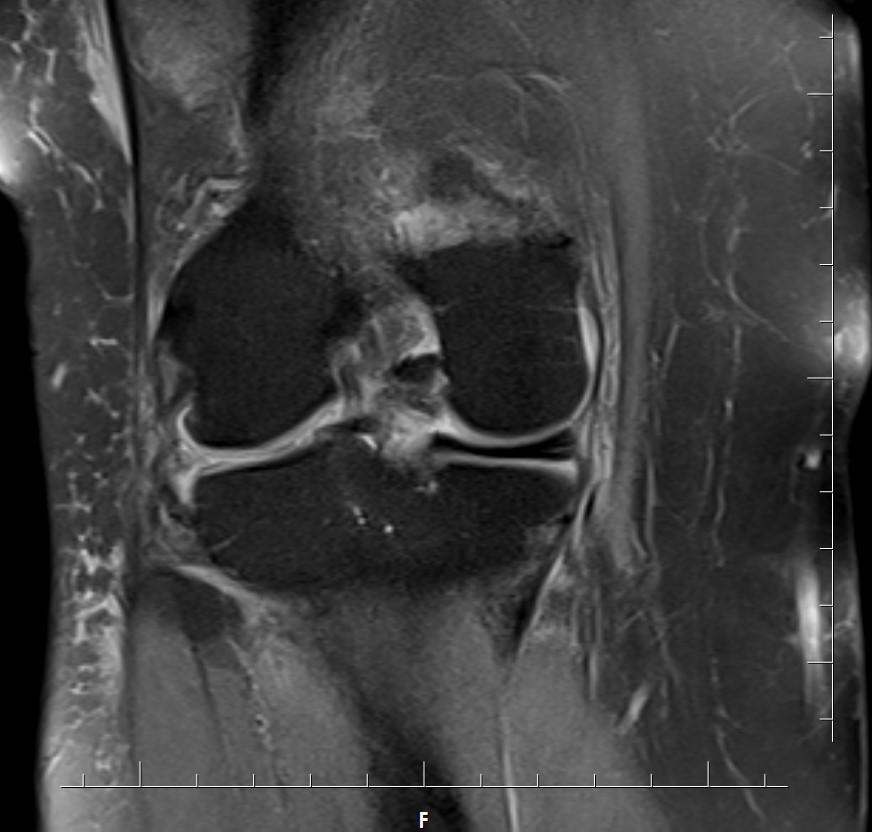

Answer: Bucket-handle tear of the lateral meniscus

Fat-suppressed images demonstrate a large displaced “handle” from the body of the lateral meniscus near the intercondylar notch.